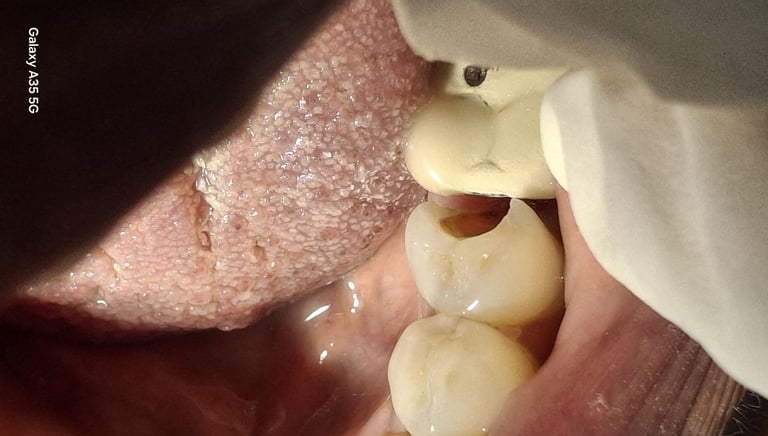

Root Canal Treatment near Shyamal, Ahmedabad

Before

After

All images shown here represent real clinical cases treated at our dental clinic with patient consent.

At Shree Dental Care, we focus on gentle, precise, and well-planned root canal treatment to remove infection, relieve pain, and preserve your natural tooth structure.

Patients from Shyamal and nearby areas of Ahmedabad visit our clinic for comfortable root canal procedures carried out using modern techniques and strict hygiene protocols. The treatment helps eliminate infection from inside the tooth, prevents further damage, and restores normal chewing function.